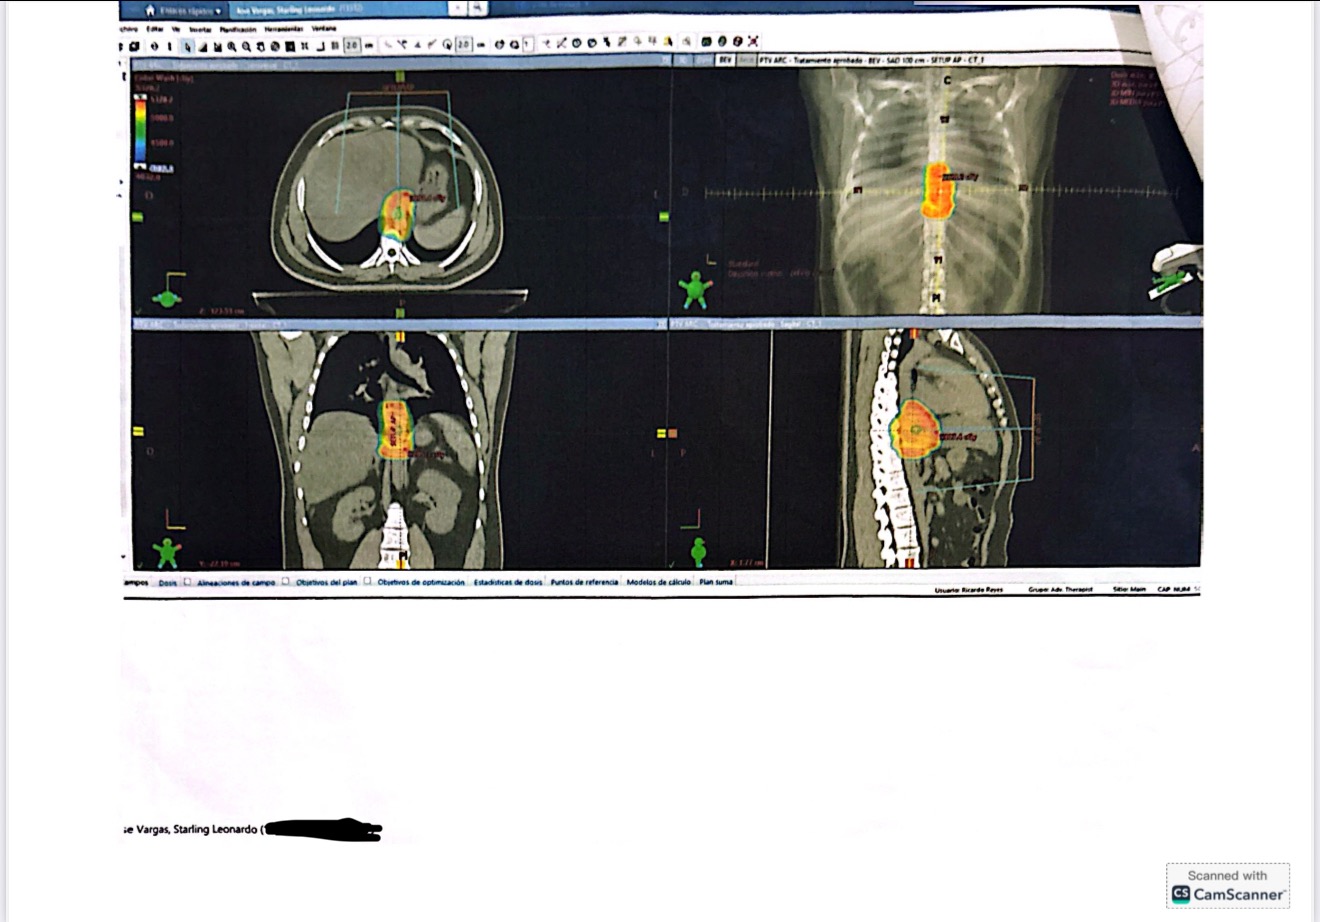

ENG// Please help Starling and his family bring him to America so he can seek proper treatment for stage 3 esophageal cancer. There is no surgery available in the Dominican Republic, where Starling is located, and his insurance does not cover the surgery he needs, so his family is trying to raise money to afford to bring him to America and seek proper help.

ESP// Por favor, ayude a Starling y su familia a llevarlo a Estados Unidos para que pueda buscar el tratamiento adecuado para el cáncer de esófago en etapa 3. No hay cirugía disponible en la República Dominicana, donde Starling está ubicado, y su seguro no cubre la cirugía que necesita, por lo que su familia está tratando de recaudar dinero para permitirse llevarlo a Estados Unidos y buscar la ayuda adecuada.